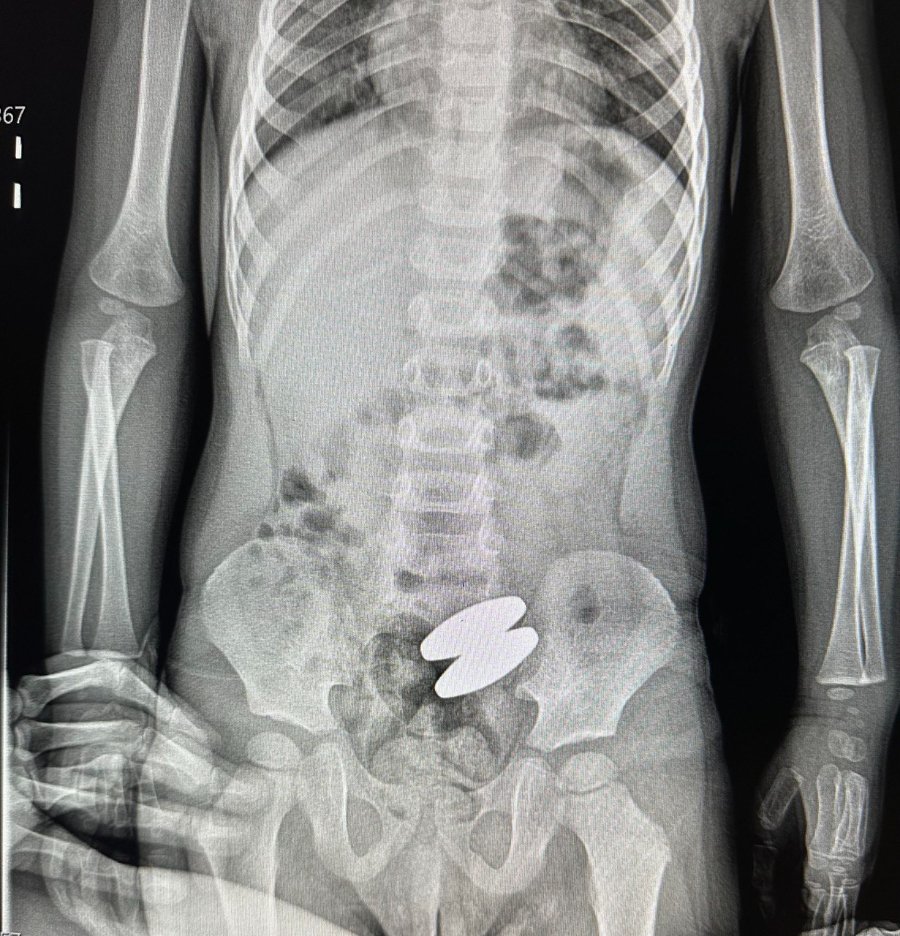

Два магніти досить великого розміру лікарі вилучили із кишківника 2-річного хлопчика на Волині.

«Я перевірила батарейки в іграшках та інші деталі. В лікарні у Володимирі, куди ми звернулися спочатку, я наголосила, що підозрюю проковтування стороннього предмету. Зробили рентген і вже на рентгені я побачила саме ті магніти з холодильника», - розповіла мама.

Хірург Василь Никитюк, який лапаросокопічно прооперував хлопчика, наголосив, що ці магніти великі й важкі, тож природньо б не вийшли. На момент операції магніти були з’єднані між собою, тисли на стінки кишківника, внаслідок чого в ділянках тиску припинилося кровопостачання — без оперативного втручання це загрожувало перфорацією. Після операції хлопчик почувається добре, на щастя, вдалося уникнути важких наслідків для його здоров'я.